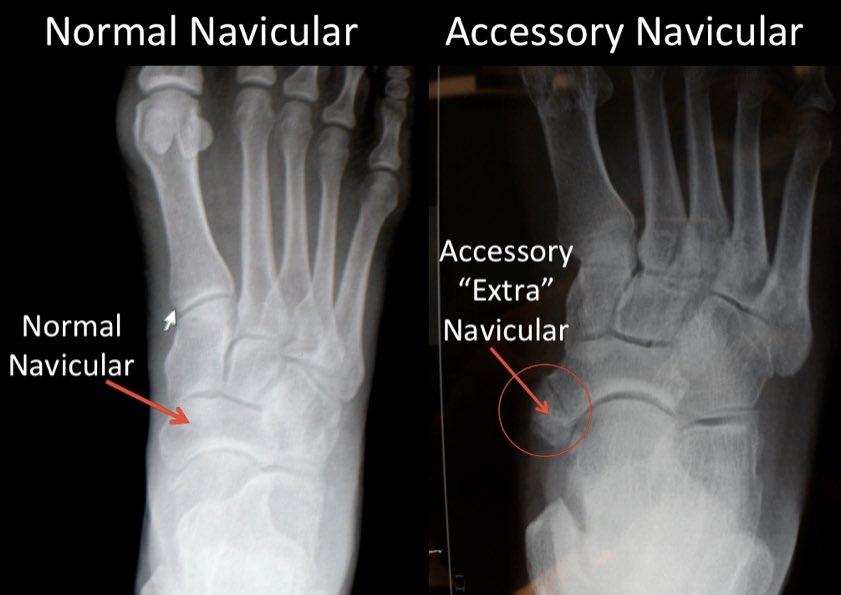

- عملية حك العظم الزورقي الزائد في مكان قوس القدم غالبًا لاينصح بها لكن ربما تكون مفيدة فقط في سن المراهقة إلى بداية العقد الثالث من العمر حسب تقييم الطبيب المختص